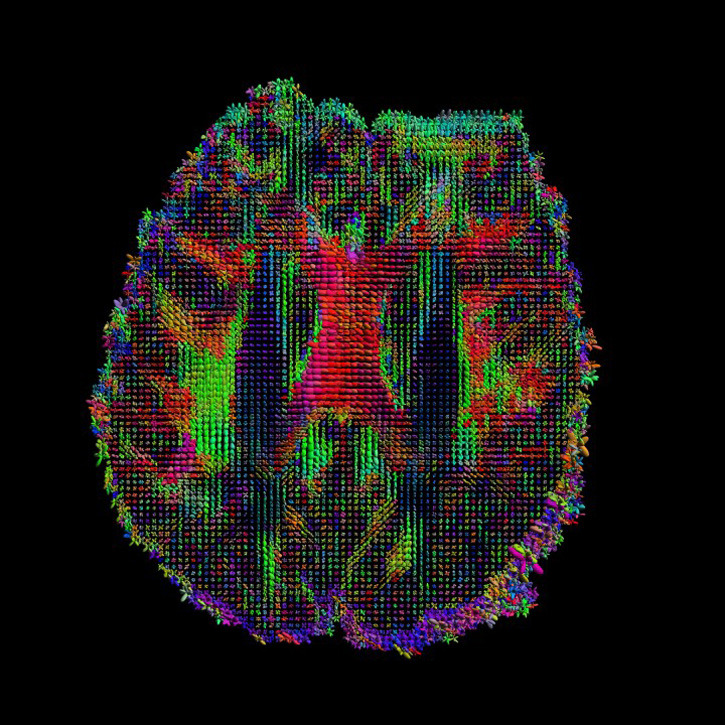

- Image: Courtesy of the Laboratory of Neuro Imaging and Martinos Center for Biomedical Imaging, Consortium of the Human Connectome Project.White matter fiber architecture from the Connectome Scanner dataset.

- Image: Courtesy of the Laboratory of Neuro Imaging and Martinos Center for Biomedical Imaging, Consortium of the Human Connectome Project. HARDI, Axial View.